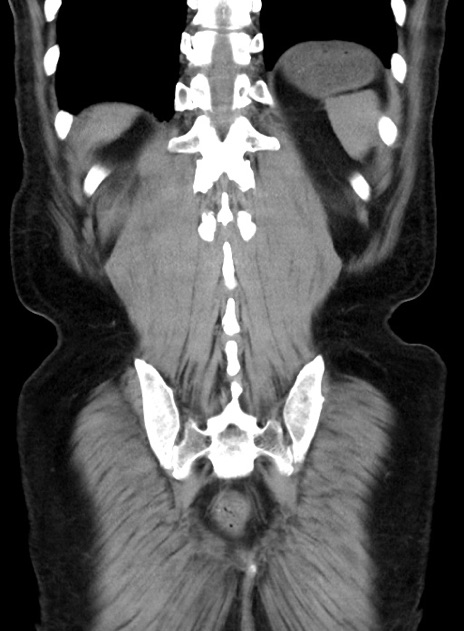

症例38(冠状断像)

【症例】70歳代 男性

【主訴】腹痛・嘔吐

【現病歴】昨晩より、嘔吐・腹痛あり。今朝になっても嘔吐あり。来院。

【既往歴】心臓バイパス手術、開腹胆摘、腸閉塞

【身体所見】BP 107/71mmHg、HR 116/min、腹部:平坦、軟、下腹部に軽度圧痛あり。反跳痛なし。

【データ】WBC 15100、CRP 0.32